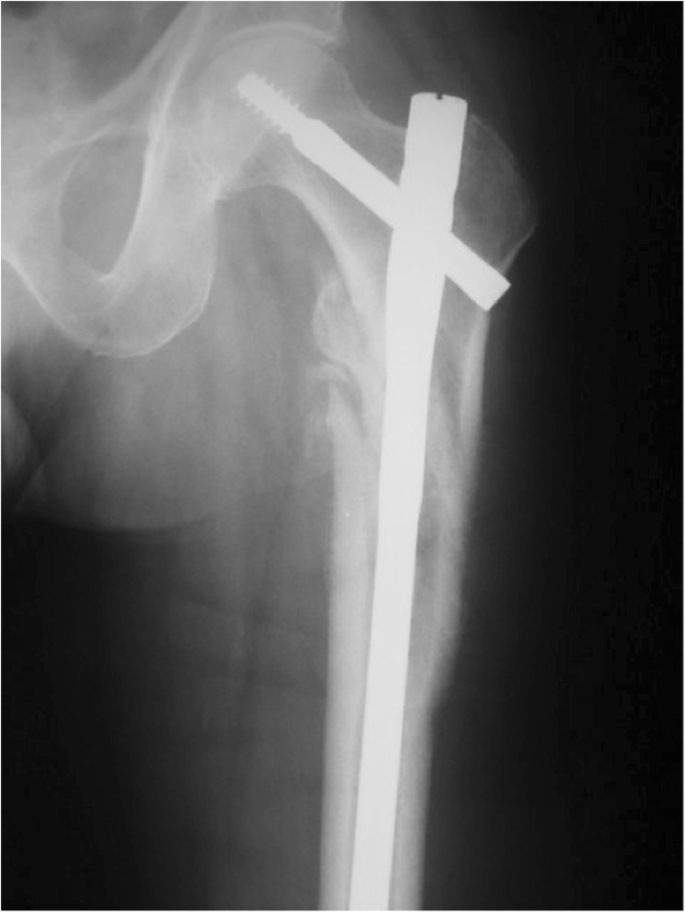

What internal fixation method has been used to internally fix this hip?

IM nail